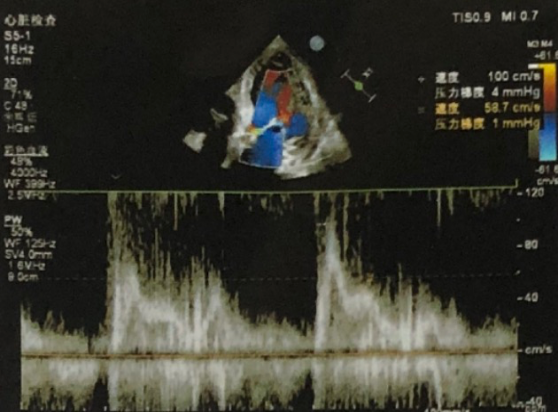

超声提示:主动脉峰值流速603cm/s,峰值压差145mmHg,EF=61%。

结论

1.主动脉瓣极重度狭窄;

2.二尖瓣、三尖瓣少中量返流;

3.左室舒张功能减低,左心扩大

4.重度肺动脉高压。

术后即刻评估

术后行主动脉根部造影未见明显夹层,压差从145mmHg降至10mmHg,无明显瓣周漏,且冠脉血流通畅;复查心脏彩超显示心功能指标较前明显提升,症状明显改善。